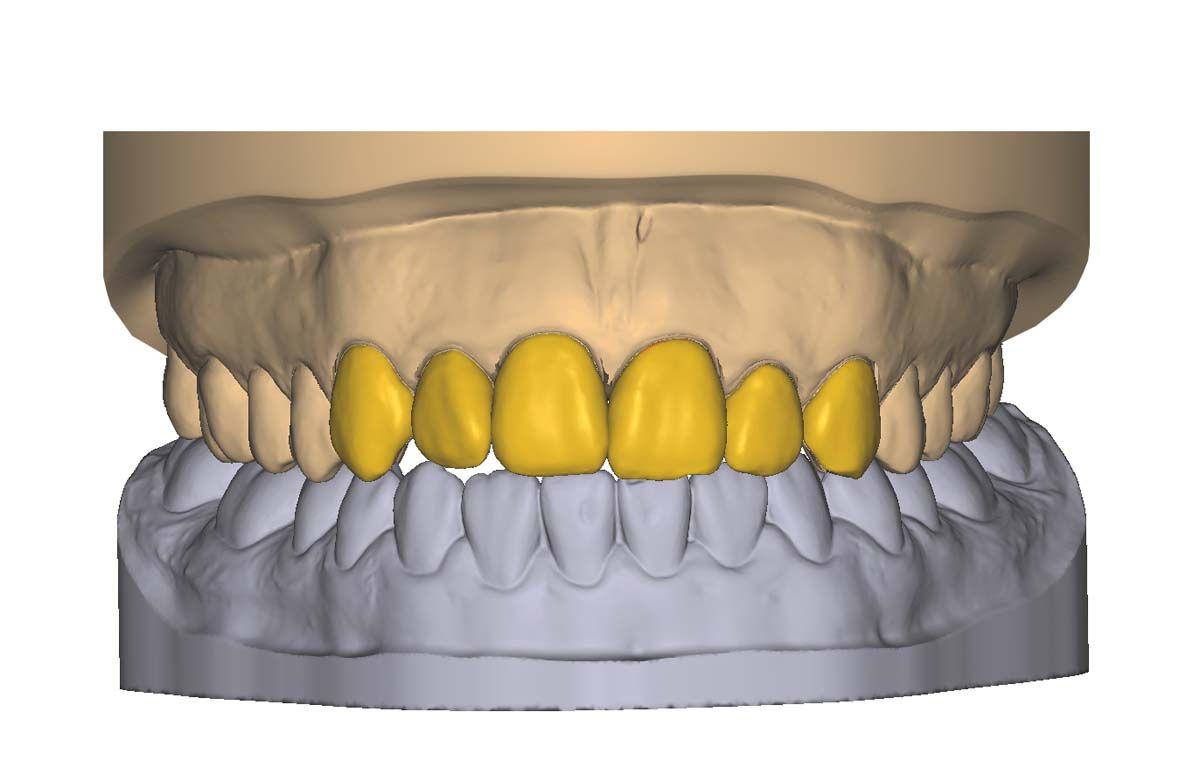

We used to try showing patients their clinical situation on 2D x-rays and demonstrating treatment using models. Later, digital intraoral cameras helped, but they could not show much more than what a patient could see in a mirror. Today, it is possible to show patients every angle of their clinical situation in hyperrealistic 3D with a CBCT scan. Now, when I recommend treatment to patients and they ask why, I am armed with an interactive image captured by my CS 8200 3D extraoral imaging system (Carestream Dental). I scroll through the tooth and bone, point out lesions below the surface, and show why there is or is not enough bone for an implant. If you use something like the Prosthetic-Driven Implant Planning module to automatically merge an intraoral scanner file with the CBCT scan, you create an even more accurate picture. How much easier is it for the patient to accept treatment when they are seeing the end results of that treatment?